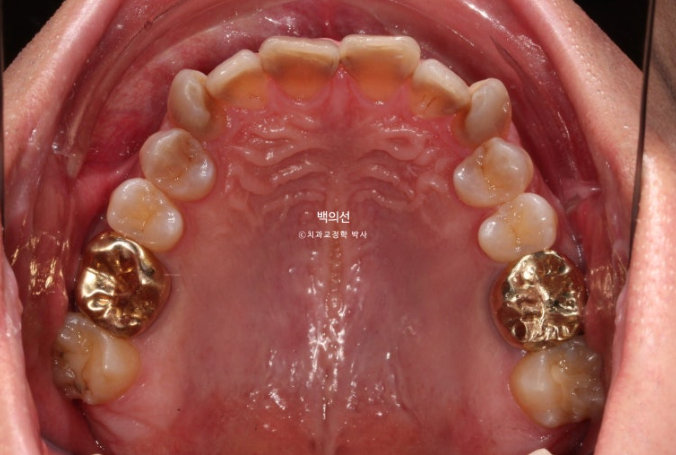

They wanted all teeth, from the canines back to the premolars, both upper 8 and lower 8, covered with laminate.

The discoloration is severe, with a fairly deep gray tone.

However, as you can see from the front, the canine crowding means laminate treatment would be difficult unless orthodontic treatment is done first.

In the lower front teeth, there are varying heights in addition to the canine crowding.

The lower front teeth have stricter conditions for no-prep laminate than the upper front teeth.

The canine crowding is fairly severe.